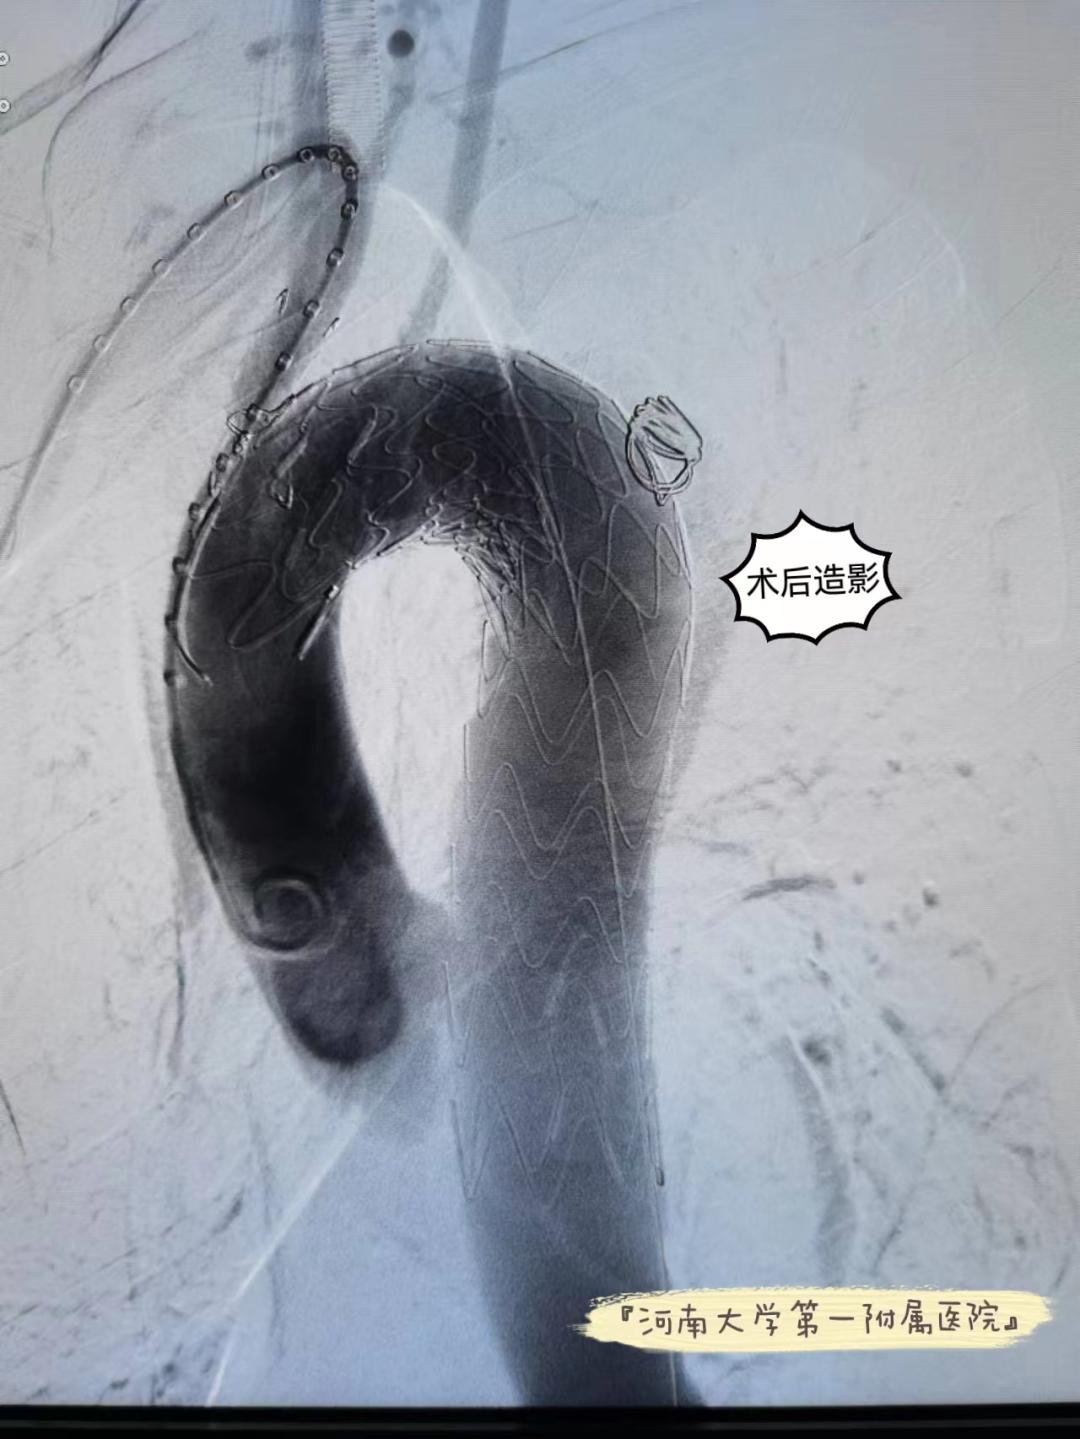

术后造影

术后患者转入重症监护室,重症医学部主任杨超针对患者病情制定了一系列切实有效的治疗措施,术后当天患者生命体征一切平稳,然后转入心血管外科病房。在心血管外科医护团队的精心治疗和护理下,患者恢复良好。术后复查CTA,胸主动脉修复良好,支架位置形态好,无内漏,患者胸痛症状消失,顺利出院。